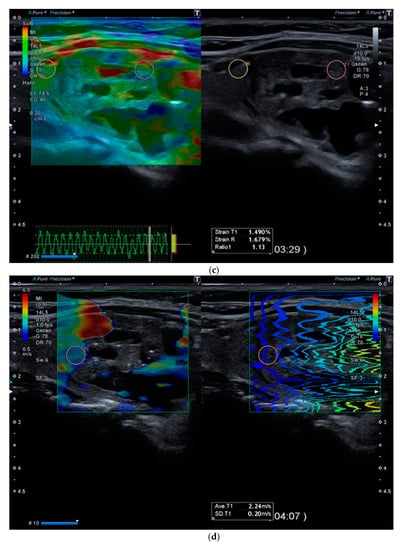

Figure 2.

(a). At B-mode Ultrasound (US), an oval-shaped nodule with mixed ecostructure, some internal fluid areas and smooth margins, was identified (EU-TIRADS 3). (b). At color–Doppler US evaluation, the lesion appeared with internal and peripheral vascularization (pattern III). (c). At Strain Ratio Elastography (SRE) evaluation, the lesion appeared soft (SR 1.13). (d). At Shear Wave Elastography (SWE) evaluation, the lesion appeared soft (2.24 m/s). (e). At CEUS evaluation, the lesion appeared solid and richly vascularized, similar to the surrounding thyroid parenchyma without wash-out. At histology, the lesion was confirmed to be a follicular hyperplasia.